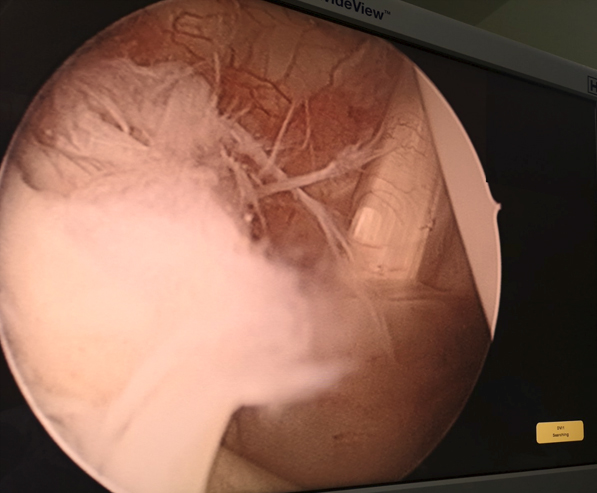

Iz foto dokumentacije dr Medenice: Uvodjenje metalnog vodiča u zglob ramena na mestu tzv. sigurne zone

Iz foto dokumentacije dr Medenice: Artroskopske slike zgloba ramena |

Artroskopska operacija ramena izvodi se specijalnim artroskopskim instrumentima, uz pomoć artroskopske kamere koja se takođe uvodi u zglob. Hirurg prati sopstveni rad na ekranu (visoke rezolucije) postavljenom sa strane, gledajući uveličanu sliku operativnog polja, koja mu obezbeđuje veću preciznost u radu.

Iako su za rame karakteristični veliki krvni sudovi i veliki živci, pri artroskopskim operacijama gotovo da nema krvarenja, kao ni oštećenja tetiva, krvnih sudova ili nerava. Artroskopija ramena je, prema rečima dr Medenice, zaista minimalno invazivna zahvaljujući tome što se artroskopska kamera i hirurški instrumenti uvode kroz vrlo male incizije (do 5 mm), takozvane portale, precizno locirane u bezbednim zonama ramena. Tačno su određeni prednji gornji i prednji donji ulaz, zadnji ulaz, prvi lateralni i drugi lateralni (bočni), kao i aksesorni portali (dodatni ulazi), pri čemu se najčešće koriste tri do četiri standardna ulaza. Artroskopska kamera se uvodi u zglob kroz zadnji portal, a zatim se kamerom nadgleda ulazak hirurških instrumenata; prvo se uvodi mala igla, da bi se otvor potom lagano širio za uvođenje takozvanog troakara, plastične vodilice kroz koju se uvode različiti hirurški instrumenti, uključujući i artropumpu (dovod i odvod sterilne vode) za ispiranje zgloba.